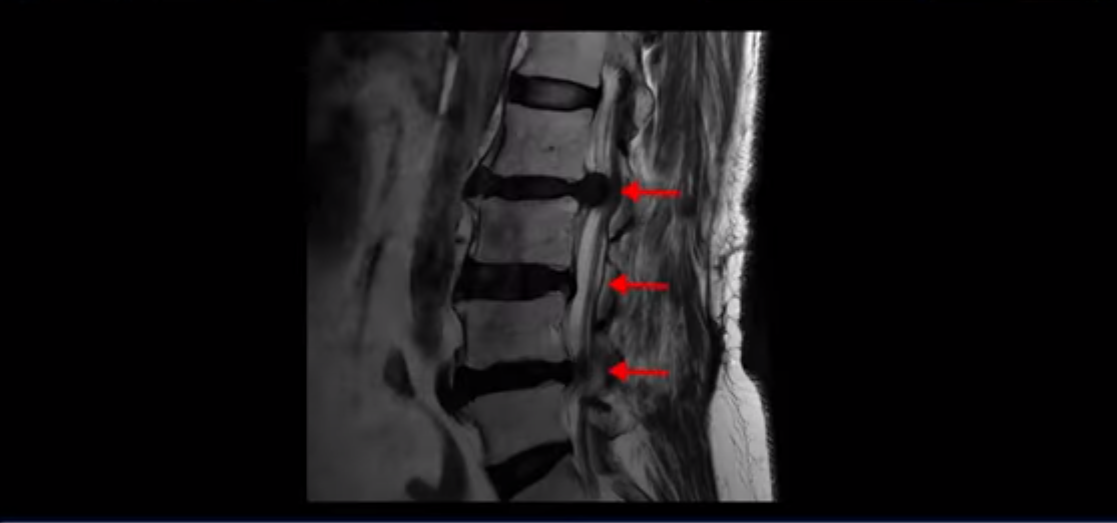

이 환자분은 고관절 쪽이 10년이 넘게 아팠고, 5년 전에는 갑자기 허벅지와 다리가 아파 못 걷게 돼서 허리 수술을 받습니다. 그리고 3년 후에 다시 재발합니다. 고관절 통증은 허리 수술 이후에도 좋아지지 않고 계속 아팠습니다. 수술하고 재발한 이후로 원래부터 아프던 고관절은 물론, 양쪽 엉덩이와 사타구니 및 허벅지가 다 아파서 잘 걷지도 못하고 또 앉거나 누워도 아파서 뒤척거리기도 힘듭니다. 이분 MRI를 보면 여러 마디가 다 안 좋습니다.

2번 3번은 디스크가 심하게 터져있고 협착까지 있습니다.

4번 5번에는 왼쪽으로 이전에 수술한 자국이 보이는데

수술한 부위에 상처 조직이 생겨 유착된 부위가 보입니다. 왼쪽, 오른쪽 신경 가지가 빠져나가는 추간공을 보면 오른쪽도 여러 마디가 좁아져 있고

왼쪽도 여러 마디가 좁아져 있습니다.

이렇게 허리 여러 마디와 신경 나가는 구멍 오른쪽, 왼쪽이 다 안 좋으니까 양쪽 엉덩이와 다리가 다 아픈 겁니다.